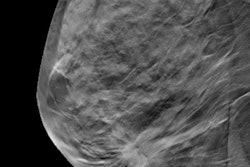

The images demonstrate how noise is reduced with the technique while the conspicuity of calcifications is maintained. Courtesy of Junchi Liu.Seven (70%) of 10 breast radiologists either preferred the virtual higher-dose DBT images over the real full-dose images or could not distinguish between the two, according to the group. The difference in image quality between the image types wasn't statistically significant (p = 0.59).